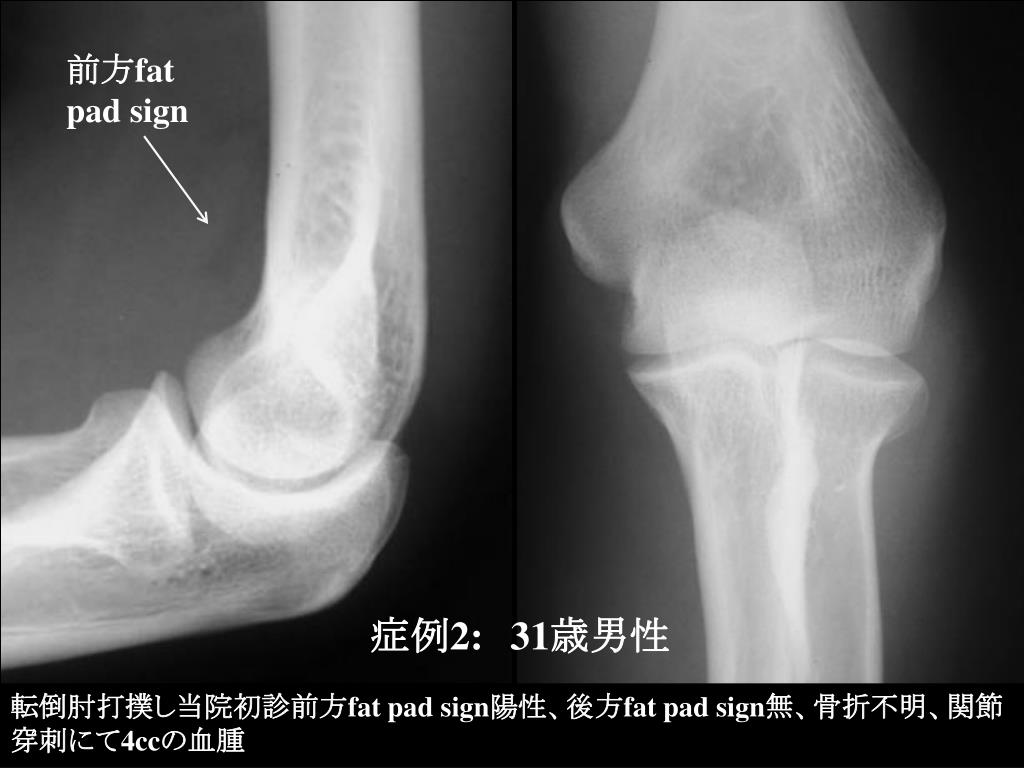

9. 前方fat pad sign 症例2:31歳男性 転倒肘打撲し当院初診前方fat pad sign陽性、後方fat pad sign無、骨折不明、関節穿刺にて4ccの血腫